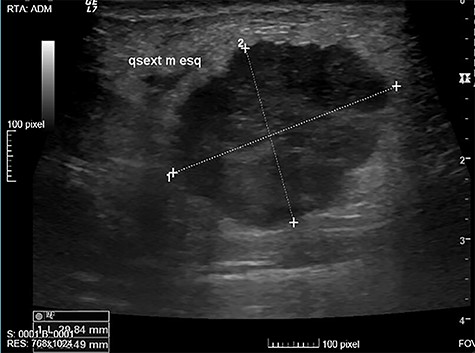

The authors report the case of a 73-year-old female patient with complaints of a left breast lump, referred to our Breast Clinic, due to a suspicious nodule of 25 mm in the upper external quadrant (UEQ) of the left breast, without suspicious axillary lymph nodes on breast ultrasound (US) (Fig. 1) and mammogram. Menarche and menopause occurred at 10 and 51 years old, respectively. Her menstrual cycles had been regular. She had had three gestations and three normal deliveries after which she breastfed. She had taken oral contraceptives but no hormone replacement therapy. She had a history of alcohol consumption and had no relevant family history. At our clinic, upon examination, she had a suspicious lump of around 30 mm in the UEQ of the left breast. The breast micro-biopsy revealed a breast tumor with abundant chondroid stroma component with necrotic areas; cells were small with an increased nucleus-to-cytoplasm ratio, hyperchromatic nuclei, positioned in a cordonal pattern (probable metaplastic carcinoma). Concerning immunohistochemistry, it was positive for AE1/AE3 and negative for BCL2, CD34 and P63. This case was presented at our Multidisciplinary Breast Tumour Board and surgery was proposed. Thus, she underwent a breast conservative surgery (BCS) (wire-guided quadrantectomy) (Fig. 2) and axillary sentinel lymph node dissection (SLND) (following de Z0011 protocol), which ran uneventfully. Intra-operative frozen section revealed negative microscopic surgical margins and three axillary lymph nodes negative for macro-metastasis. Metallic clips (of titanium) were applied in the margins of the quadrantectomy. She had an uneventful recovery and was discharged home on the third post-operative (PO) day. The definite pathological report (Fig. 3) revealed an invasive breast carcinoma, of metaplastic type, with mesenchymal differentiation (chondroid), intermediate (2) grade, triple-negative, with 31-mm, negative microscopic surgical margins and three axillary lymph nodes negative for metastasis, pT2N0 (sn). The tumoral lesion was a proliferation with infiltrative margins, presenting a peripherical component of trabecular and cordonal pattern, composed by small cells with ill-defined margins and hyperchromatic nuclei. Pleomorphism was moderate, exhibiting relatively frequent mitosis’ figures. It exhibited transition to a matrix of chondroid features, centrally positioned, abundant, with features of maturity. Peripherally, there were no tumoral veno-lymphatic emboli, images of peri-neuronal infiltration nor necrotic areas, but there was a component of in situ carcinoma. Concerning immunohistochemistry, it was positive for vimentin, CK 5/6 and 7, p63 and GATA3, but negative for smooth muscle actin, calponin, CK 20, S100 protein, hormonal (estrogen and progesterone) receptors and human epidermal growth factor receptor 2 (HER2). The proliferative index, assessed by the Ki67, was of 80% on the trabecular component. She had a thoracic, abdominal and pelvic computed tomography done, which did not show any additional disease. This case was presented again at our Multidisciplinary Tumour Board, where chemoradiotherapy was proposed. The chemotherapy protocol proposed was 4 cycles of doxorubicin 96 mg and cyclophosphamide 965 mg each 21 days, followed by 12 cycles of weekly taxane.

Suspicious nodule of 25 mm, in the UEQ of the left breast on breast US.